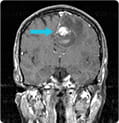

Intraventricular Tumor X RayNeuroendoport Surgery for Intraventricular Tumor(Subependymoma)

With an intraventricular tumor nearly two inches in diameter, a 47-year-old man suffered from relentless headaches, confusion, and visual disturbances. Read how UPMC surgeons used Neuroendoport surgery, with minimal manipulation of the surrounding brain, to relieve the patient’s symptoms and preserve his speech and vision.